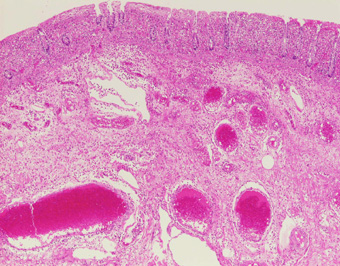

| 大腸粘膜の浮腫,出血,上皮の変性,炎症細胞浸潤をみとめる.(HE,×4) |